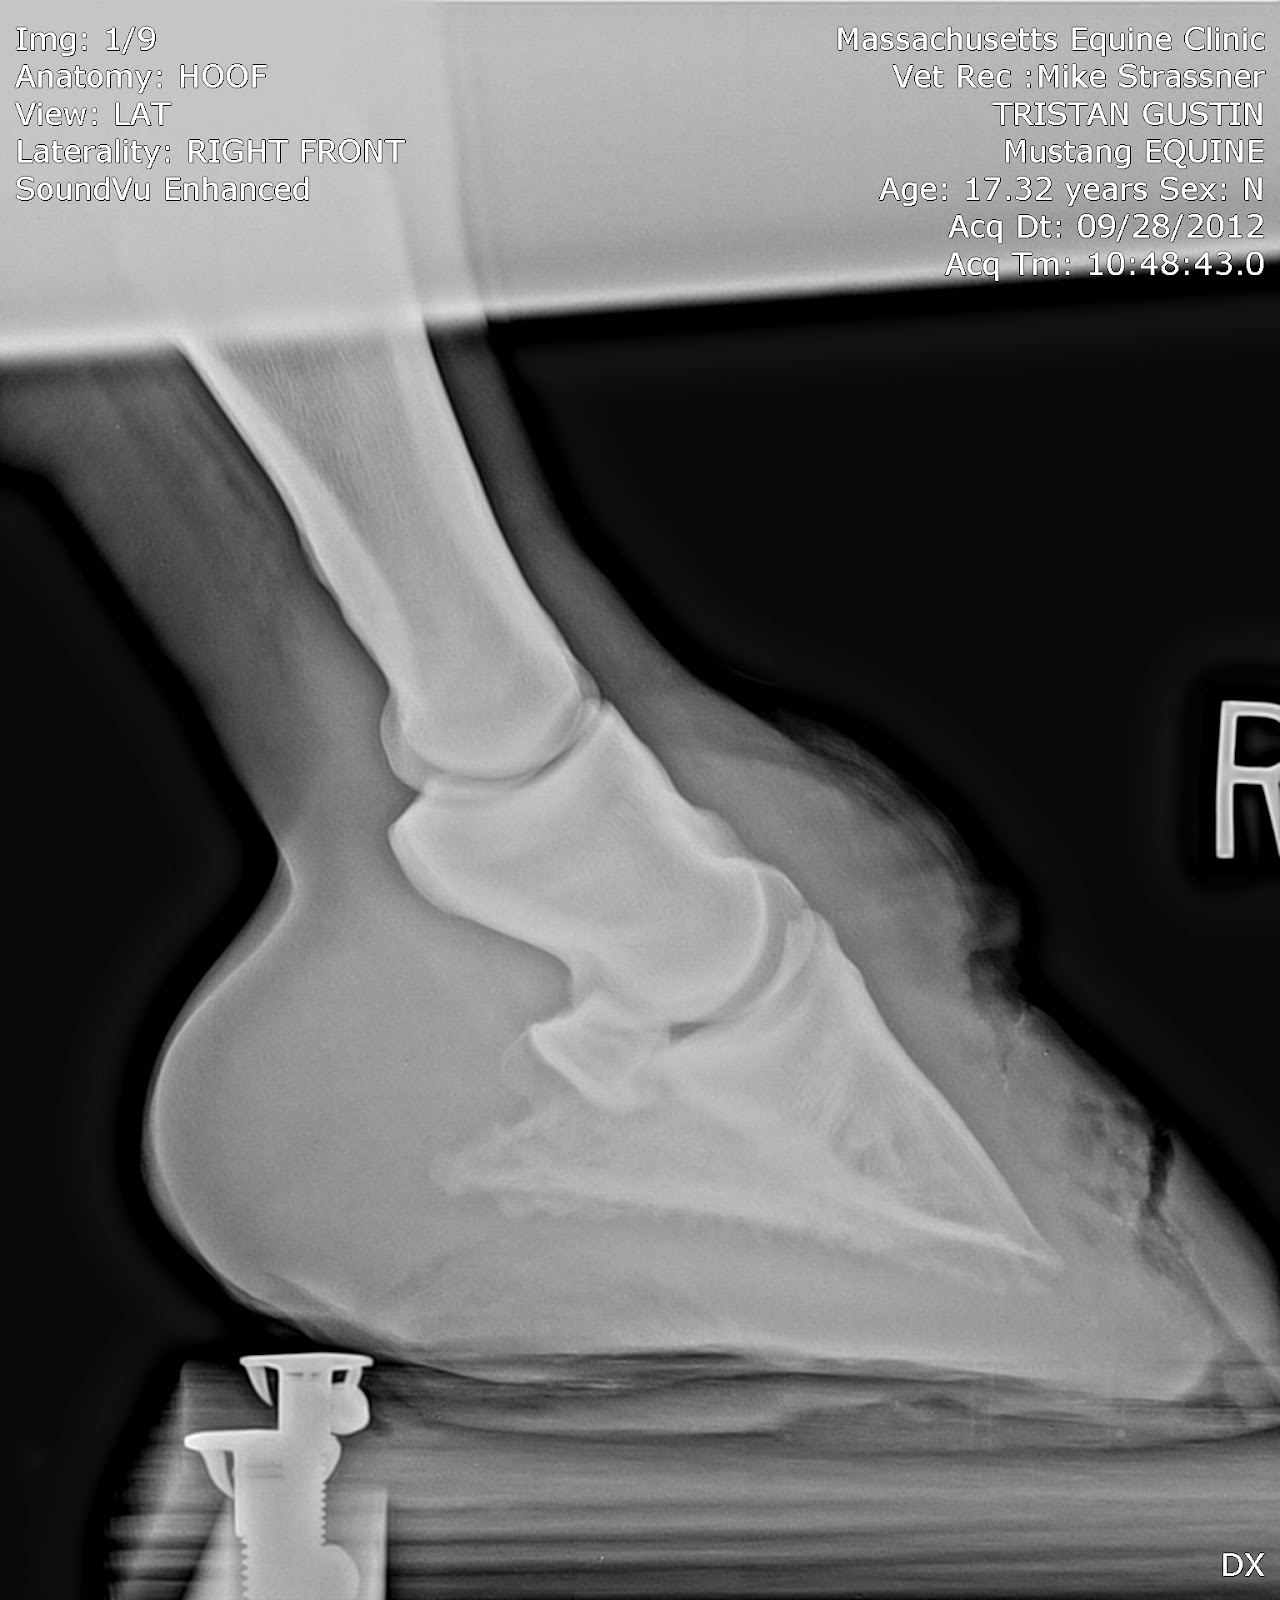

| And now, with holes. You can see the top hole, and the bottom hole, and the track all the way down to the sole. |